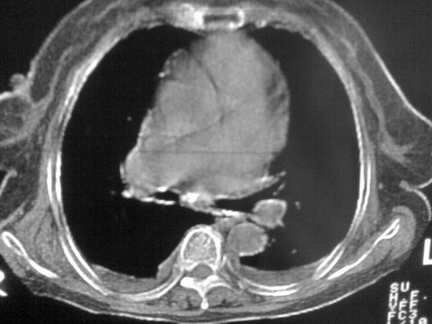

缩窄性心包炎

左室为主的心脏增大。

右肺感染;双侧胸腔少量积液,心影增大,可能与心功不全有关;胸内甲状腺肿。

右肺炎性变,双侧甲状腺肿,胸膜肥厚,心影增大考虑心功能不全.

以下是引用zjzjr在2008-4-29 13:57:00的发言:[br]右肺感染;双侧胸腔少量积液,心影增大,可能与心功不全有关;胸内甲状腺肿。

胸内甲状腺肿;右肺中叶感染;双侧胸腔少量积液;心影增大,考虑有心功能不全。